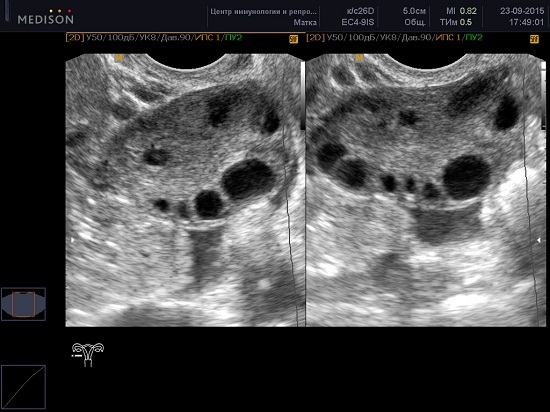

Доза рассчитывается индивидуально исходя из целей и задач. Идеальное попадание 12-14 фолликулов. Если замораживаем яйцеклетки - 18-20.

Стимулированный яичник